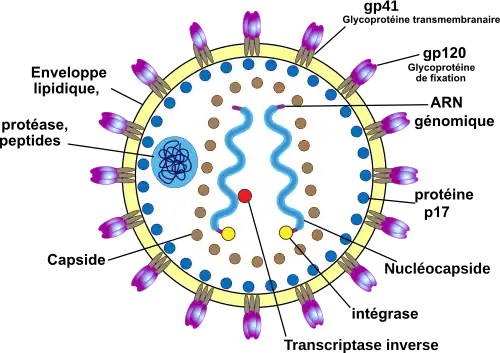

Le VIH-1 est un virus sphérique d'un diamètre moyen de 145 nanomètres[42]. Comme de nombreux virus infectant les animaux, il dispose d'une enveloppe composée d'un fragment de la membrane de la cellule infectée. Dans cette enveloppe lipidique sont insérés des trimères de glycoprotéine d’enveloppe (Env). Chaque protéine Env est formée de 2 sous-unités : une sous-unité de surface gp120 et une sous-unité transmembranaire gp41. La surface d’un virus VIH contiendrait en moyenne seulement 14 trimères Env[43]. Lors de l'attachement du virus à la cellule, la protéine Env gp120 se lie à un récepteur CD4 présent à la surface des cellules CD4+ du système immunitaire. C'est pour cette raison que le VIH n'infecte que des cellules ayant ce récepteur à leur surface, qui sont en très grande majorité les lymphocytes CD4+.

À l'intérieur de l'enveloppe, se trouve une matrice protéique (MA) composée de protéines p. 17 et, encore à l'intérieur, la capside (CA) composée de protéines p. 24. C'est ce dernier type de protéines qui, avec gp41 et gp120, sont utilisés dans les tests VIH western blot. Les protéines nucléocapside p. 7 (NC) protègent l'ARN viral en le recouvrant. La protéine p. 6 est exclue de la capside et se trouve entre la matrice et la capside, elle permet la sortie par bourgeonnement des virus nouvellement formés dans la cellule.

Le génome du VIH, contenu dans la capside, est constitué d'un simple brin d'ARN en double exemplaire (9181 nucléotides)[44], accompagné d'enzymes :

- la transcriptase inverse p. 66/p. 51 ou rétrotranscriptase qui rétrotranscrit l'ARN viral en ADN viral ;

- l'intégrase p. 32 qui intègre l'ADN viral à l'ADN cellulaire ;

- la protéase p. 12 qui participe à l'assemblage du virus en clivant les précurseurs protéiques Gag p. 55 et Gag-Pol p. 160. La protéase est présente dans la capside[45].

Ces trois enzymes sont les principales cibles des traitements antirétroviraux, car elles sont spécifiques aux rétrovirus.

Le génome du VIH est composé de neuf gènes. Les trois principaux sont gag, pol et env, qui définissent la structure du virus et sont communs à tous les rétrovirus. Les six autres gènes sont tat, rev, nef, vif, vpr et vpu (ou vpx pour le VIH-2), qui codent des protéines régulatrices.